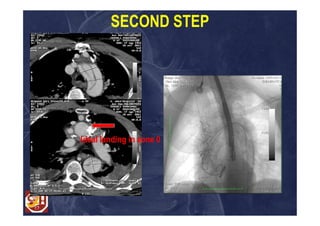

SECOND STEP

Ideal landing in zone 0

Case 2: surgicalstrategy Bentall operation; Aortic arch replacement in Z1; Proximal reimplantation of cerebral vessels; Creation of an optimal landing zone for TEVAR C-Tag Gore 34-34-200